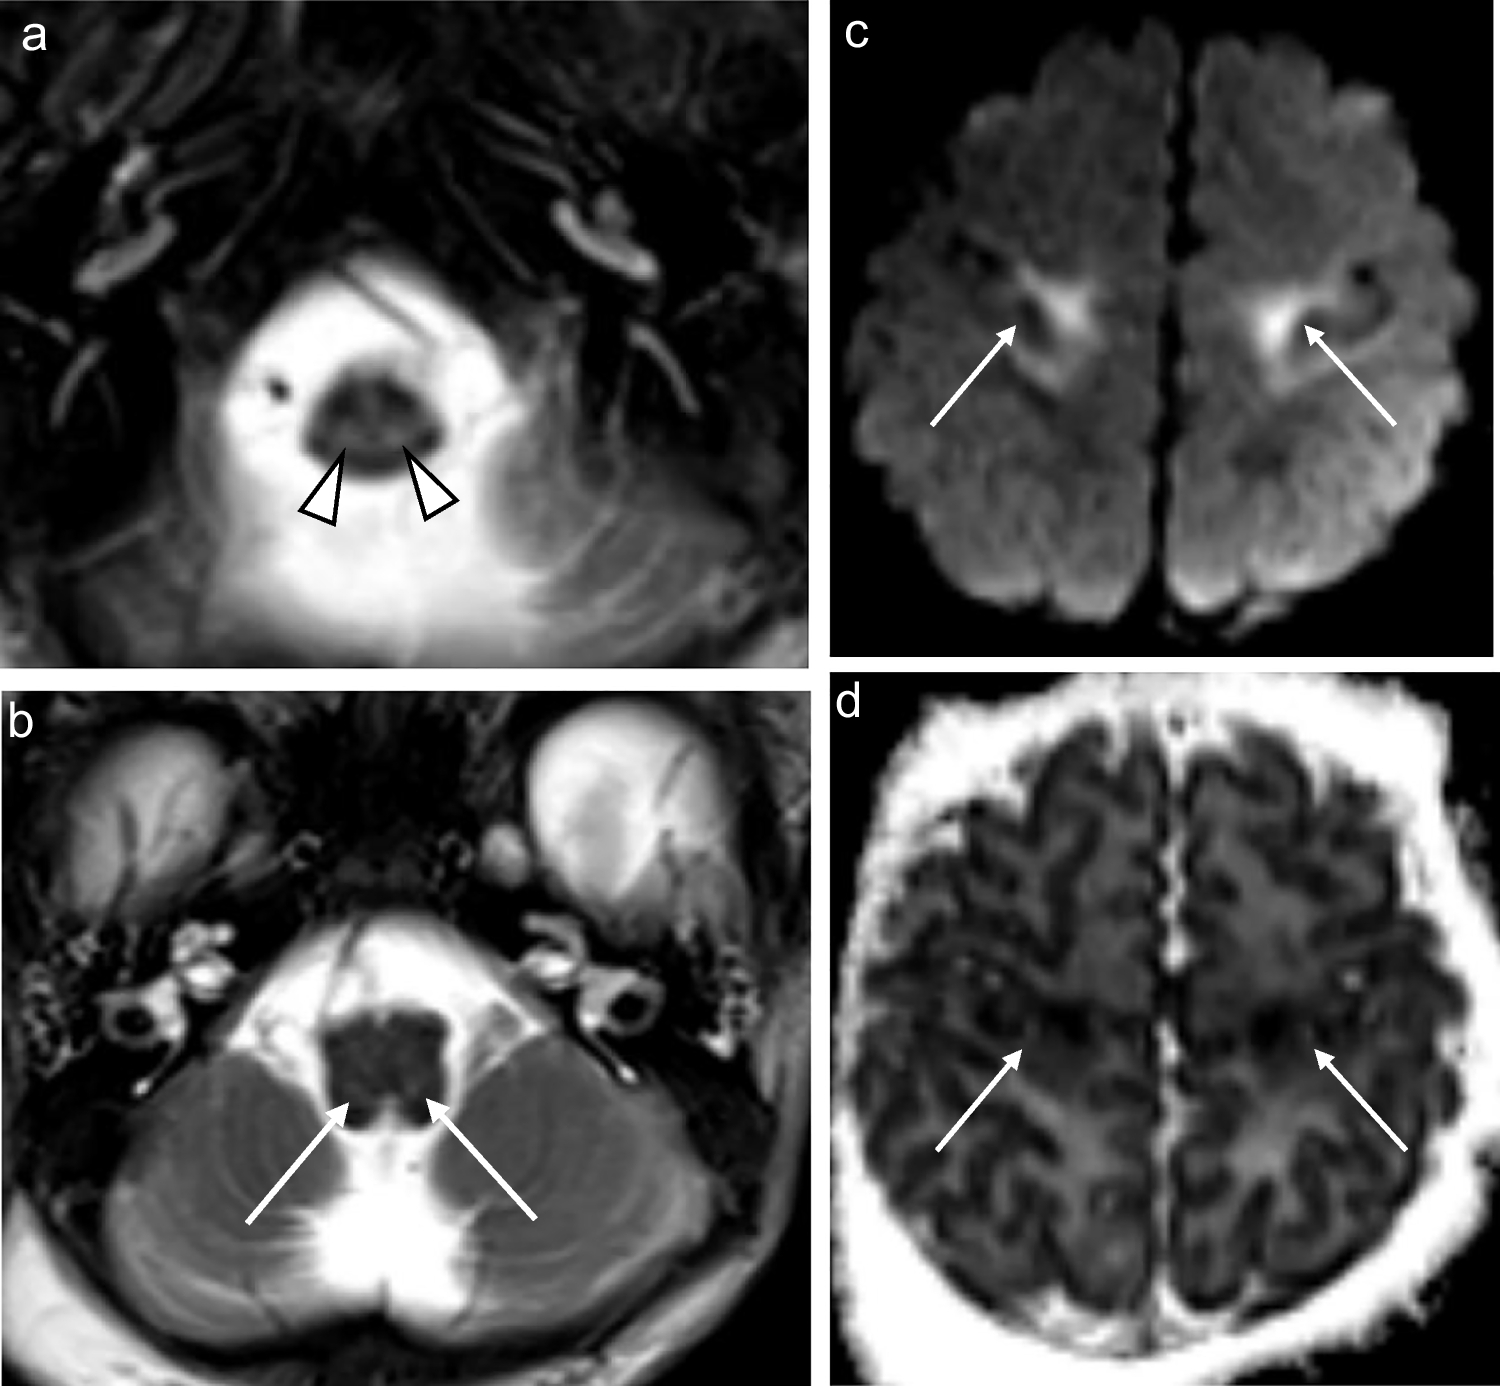

Fig. 3

A 5-week-old girl with genetically confirmed MPV17-related mitochondrial depletion syndrome. a Axial T2-weighted image shows hyperintense signal in the reticulospinal tracts of the proximal cervical cord (arrowheads). b Axial T2-weighted image shows hyperintense signal in the reticular formation of the medulla (arrows). c Axial T2-weighted image shows extensive white matter disease involving the periventricular, deep, and subcortical white matter with extension into the U-fibers (asterisks). d Susceptibility-weighted imaging reveals blooming at the site of maximally diseased white matter (arrow)

Supratentorial white matter

Supratentorial white matter disease was detected in five of eight (62.5%) patients (Figs. 2, 3, 6 and 7). Both neonates demonstrated T2 hyperintensity and restricted diffusion in the central corticospinal tracts (sub-perirolandic, corona radiata), extending more caudally into the posterior limbs of the internal capsule in one case (Figs. 1 and 2). The 5-week-old preterm infant with a corrected gestational age of 37 weeks presented radiologically as diffuse, asymmetrical leukoencephalopathy with a dorsal gradient, characterised by T2 hyperintensity in the periventricular, deep, and subcortical white matter which extended into the U-fibres (Fig. 3). No normal T1 hyperintense myelin was present in the immature brain. A focus of blooming appeared on susceptibility-weighted imaging in the maximally affected right occipital lobe white matter. The MRI study of the second 8-month-old revealed diffuse leukoencephalopathy, again with a dorsal gradient, characterised by diffusion restriction in the subcortical white matter, posterior limbs of the internal capsules, and dorsal aspects of the external capsules and fornices (Fig. 6). The second 8-month-old infant manifested marked, posterior-predominant white matter diffusion restriction involving the posterior limbs of the internal capsules, and occipital more than frontal deep and subcortical white matter, as well as the splenium of the corpus callosum (Fig. 7). The neonates and 5-week-old had corpus callosum biometry within normal limits for age [12]. Evaluation of the callosal myelination status was confounded by the presence of leukoencephalopathy in most cases but there was no significant deafferentation atrophy at the time of imaging or developmental anomalies.